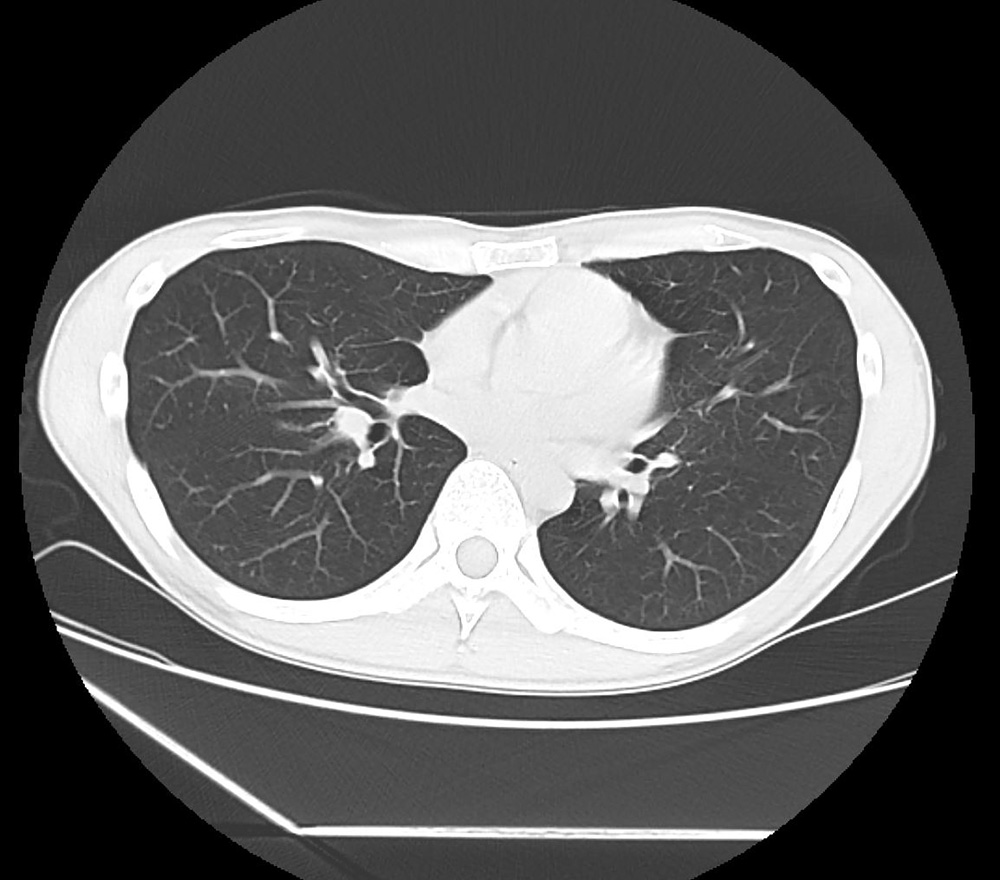

CT検査

体の断面画像を撮影し、

臓器や血管、骨の状態を

立体的に確認

X線を多方向から照射し、コンピュータで解析することで体の断面を画像化する検査です。腫瘍や炎症、出血、骨折などを高精度に診断できます。レントゲンでは分かりにくい異常も見つけやすく、短時間で広範囲を撮影できるため救急時にも有効です。造影剤を用いることで血管や臓器の輪郭をさらに鮮明に映し出し、病気の広がりや重症度を評価することができます。